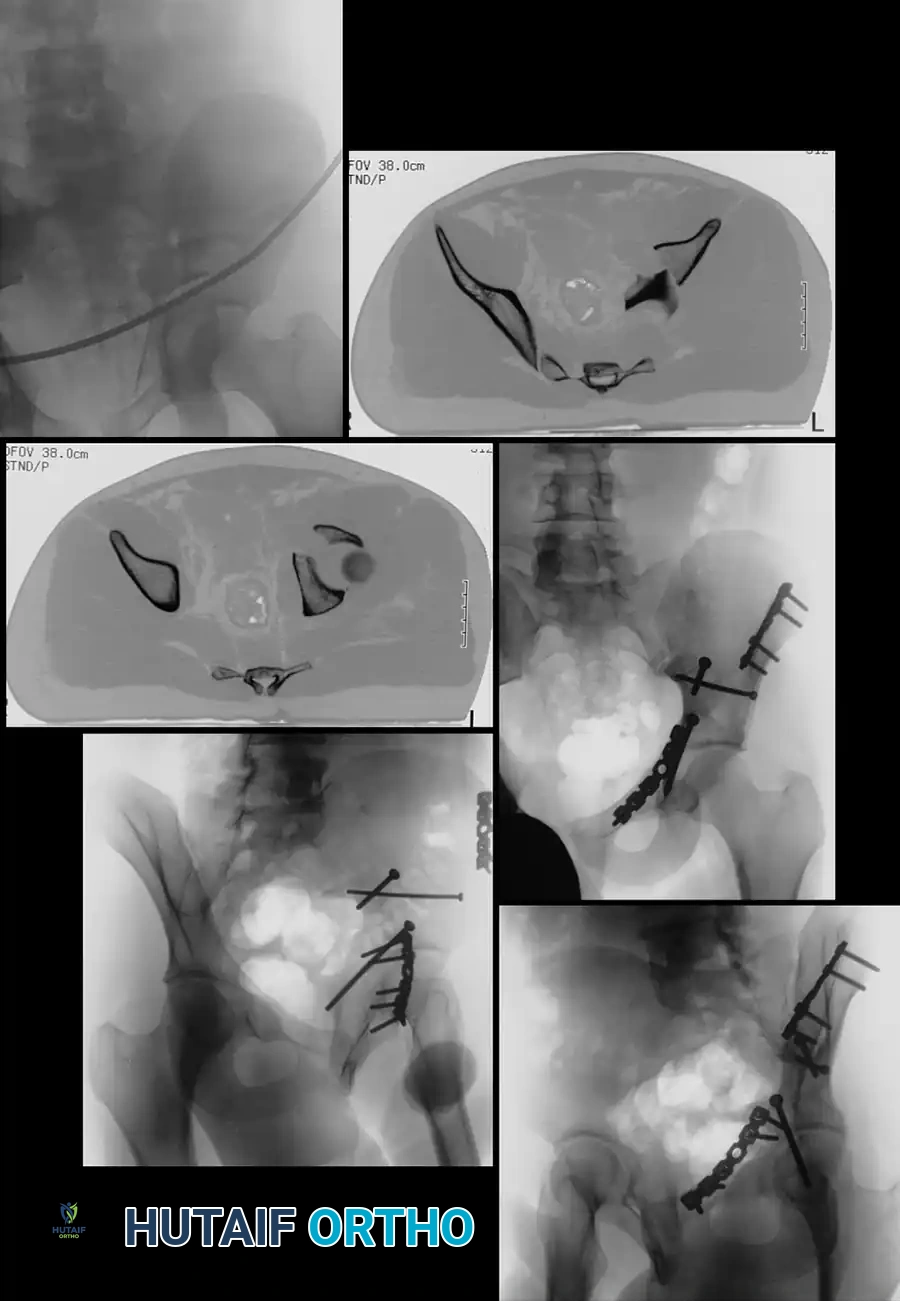

FIGURE 56-33: Anterior column fracture with quadrilateral surface comminution treated through an ilioinguinal approach with the Stoppa interval utilized to stabilize the quadrilateral surface.

Both-Column Fractures and Indirect Reduction

Both-column fractures represent complete dissociation of the articular surface from the axial skeleton. These complex injuries often require extensive exposures or combined approaches. However, when treated through an ilioinguinal approach, indirect reduction techniques are frequently employed to restore the acetabular dome, with fixation placed on the internal surfaces of the pelvis to buttress the columns.

FIGURE 56-34: Both-column acetabular fracture treated through an ilioinguinal approach with indirect reduction of the acetabulum and fixation placed on the internal surfaces of the pelvis.

The Critical Role of Postoperative Computed Tomography (CT)

Historically, reduction quality was assessed using the three standard Judet radiographic views (AP pelvis, obturator oblique, and iliac oblique). However, plain radiographs lack the sensitivity required to detect small, clinically significant incongruencies.

- Radiographic Deception: Moed et al. demonstrated that while anatomical reductions were seemingly obtained in 97% of posterior wall fractures based on plain radiographs, 16% of these cases had an intra-articular incongruity or gap of 2 mm or more when evaluated by postoperative CT.

- Standard of Care: CT is vastly superior in identifying postoperative gaps, step-offs, and retained intra-articular hardware. Consequently, postoperative CT is now strongly recommended as the gold standard for the definitive assessment of operative reduction in acetabular trauma.